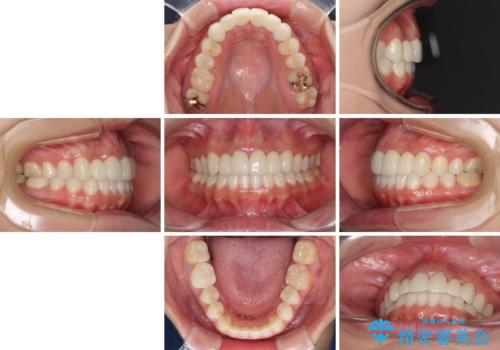

矯正治療により下顎前歯を整列させたため、上顎前歯のセラミックブリッジを補綴することで口元を少し下げることができました。

ヒトの目線がいつも口元に向けられているように感じることがなくなり、患者様には大変満足していただきました。